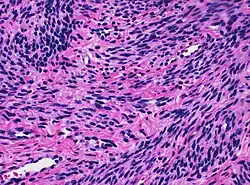

![]() Histology of myometrium | |

The myometrium is the middle layer of the uterine wall, consisting mainly of uterine smooth muscle cells (also called uterine myocytes[1]) but also of supporting stromal and vascular tissue.[2] Its main function is to induce uterine contractions.

The myometrium is located between the endometrium (the inner layer of the uterine wall) and the serosa or perimetrium (the outer uterine layer).

The inner one-third of the myometrium (termed the junctional or sub-endometrial layer) appears to be derived from the Müllerian duct, while the outer, more predominant layer of the myometrium appears to originate from non-Müllerian tissue and is the major contractile tissue during parturition and abortion.[1] The junctional layer appears to function like a circular muscle layer, capable of peristaltic and anti-peristaltic activity, equivalent to the muscular layer of the intestines.[1]

The molecular structure of the smooth muscle of myometrium is very similar to that of smooth muscle in other sites of the body, with myosin and actin being the predominant proteins.[1] In uterine smooth muscle, there is approximately 6-fold more actin than myosin.[1] A shift in the myosin expression of the uterine smooth muscle may be responsible for changes in the directions of uterine contractions during the menstrual cycle.[1]